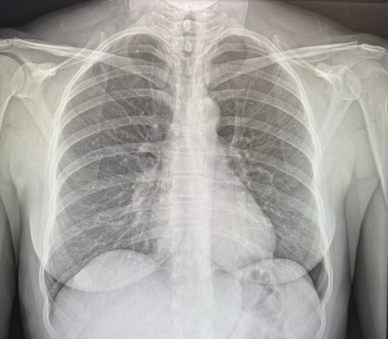

Example of a digital chest X-ray used to evaluate the heart and lungs.